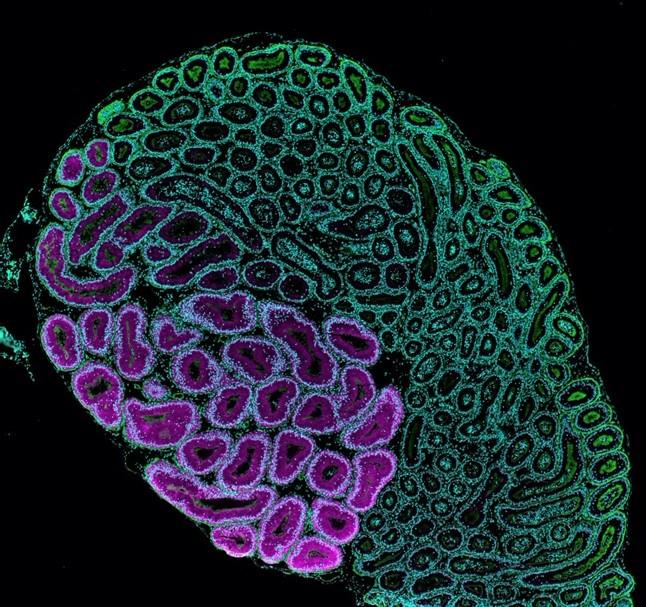

Sperm are produced in the seminiferous tubules of the testis and transit through the epididymis, a long, convoluted tube linked to the vas deferens. When the sperm enter the epididymis, they are not motile and are incapable of fertilization; however, in their passage through the epididymis, the sperm are provided an appropriate environment for maturation and storage pending ejaculation.

The research team observed that spermatogenesis proceeds normally in Nell2 knockout mouse testes but their epididymis was poorly differentiated, similar to Ros1 knockout mice. Following mating, neither Nell2 knockout nor Ros1 knockout spermatozoa can enter the uterine tubes or fertilize an egg. Further investigation showed that the Nell2 knockout epididymis is incapable of making a key protease, OVCH2, that processes a sperm surface protein, ADAM3, essential for male fertility.